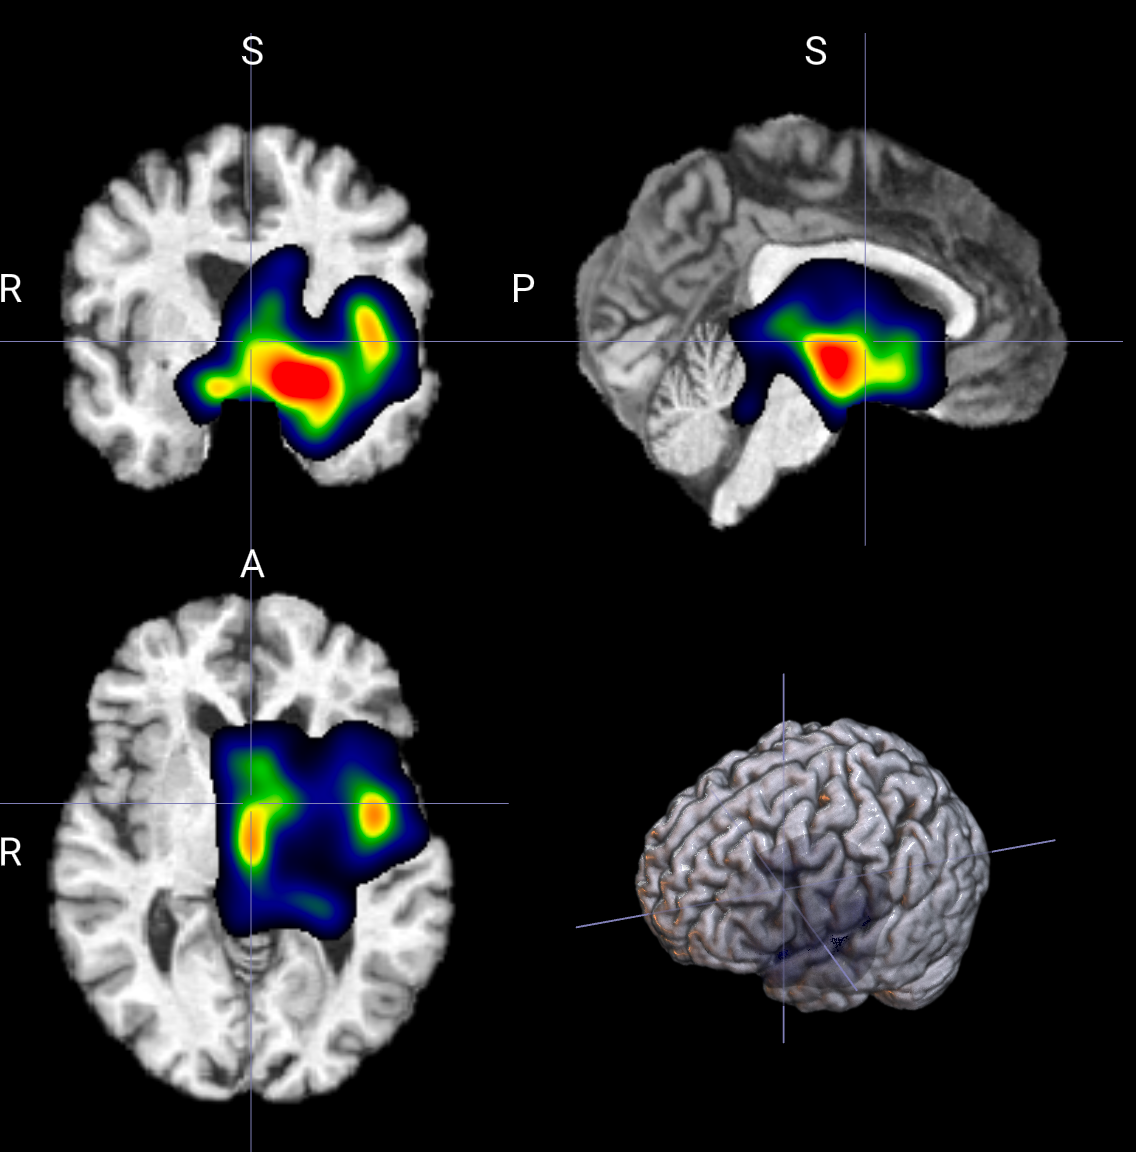

输出示例